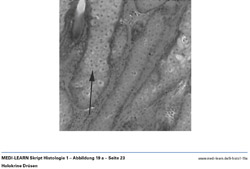

• EM-Bild einer Muskelzelle